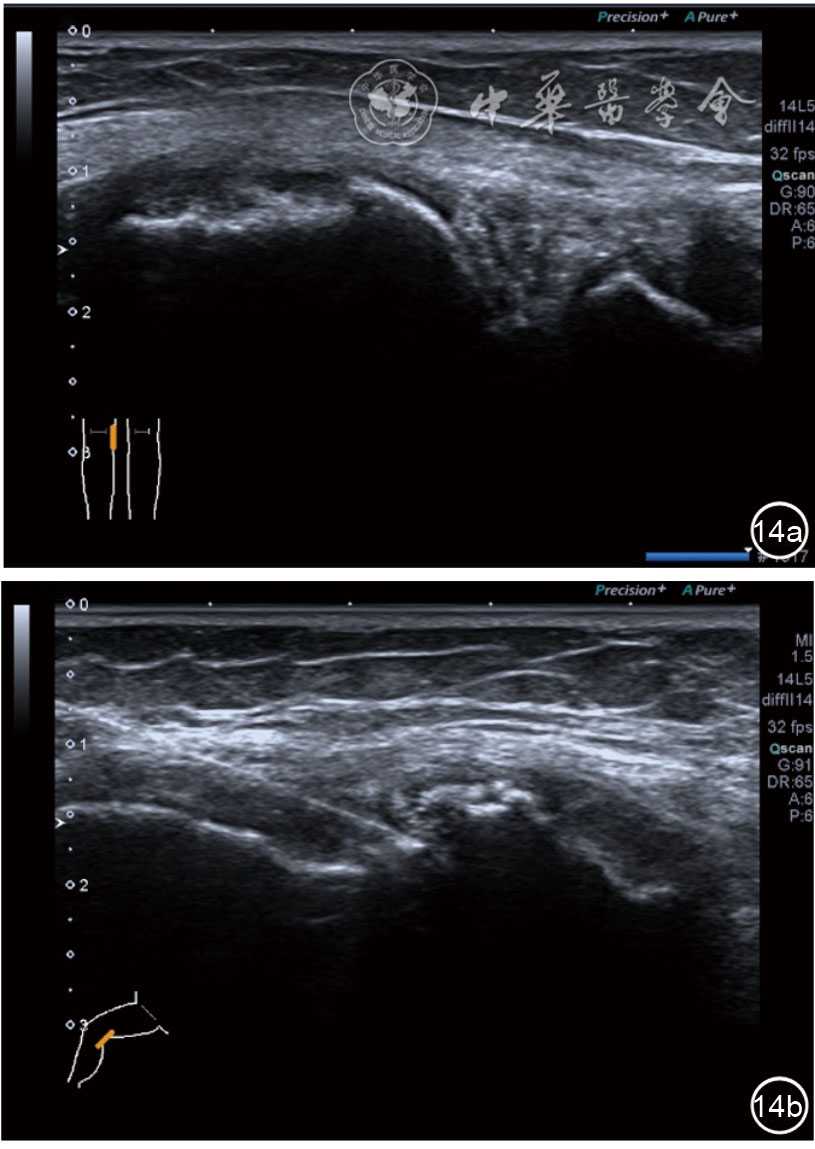

2.膝关节静态结构治疗。动力平衡失调后,继发静态结构变化,出现内外侧副韧带、交叉韧带、脂肪垫、半月板等结构变化。这里介绍半月板与交叉韧带的处理。(1)膝关节静态结构半月板治疗。在膝关节骨关节炎中主要是突出和损伤。突出主要发生于膝内翻引起的内侧半月板突出,引起内侧副韧带的张力增高。内侧半月板与内侧副韧带相连,是引起膝关节内侧疼痛的主要原因之一。治疗主要是针刀剥离松解,部分损伤可行PRP注射。①半月板突出针刀剥离松解治疗。针刀治疗主要是松解和减压,缓解疼痛,不能复位。以内侧半月板突出治疗为例。患者平卧位,髋轻度外展外旋,膝关节屈曲30°,膝下垫一软枕。选用10 MHz超声探头,穿刺区域常规消毒,探头涂抹耦合剂后套入无菌手套碘伏消毒或使用无菌耦合剂。将探头置于患者皮肤表面,内侧关节间隙长轴扫查,找到半月板突出最高点,用25G针头,抽吸1%利多卡因3 ml逐层麻醉直到半月板。选用直径1 mm的Ⅰ型2号针刀从头侧向足侧方向在内侧副韧带与半月板之间,以及半月板内部进行剥离松解3~5刀拔出针刀(图13),局部压迫5分钟,无菌敷料覆盖。②半月板损伤PRP注射治疗。半月板损伤主要表现为髌下痛,伸膝加重,查体在髌下髌韧带与侧副韧带之间,沿关节间隙有固定或局限性压痛,伸膝过程中尤为明显。MRI可示半月板断裂、损伤。如果出现绞索,严重影响功能需手术治疗。半月板损伤治疗,以注射PRP修复为主。以内侧半月板后角损伤为例。患者俯卧位,治疗前准备同半月板突出针刀剥离松解治疗。选用25G注射针头,抽取1%利多卡因2 ml局部麻醉后,制取1.5 ml PRP,穿刺到达半月板撕裂处注射,注射完毕后出针(图14),局部压迫2分钟,无菌敷料覆盖。(2)膝关节静态结构交叉韧带治疗。膝关节骨关节炎交叉韧带损伤多为部分损伤,治疗早期主要为药物或PRP注射,效果不佳时针刀做止点松解。①后交叉韧带损伤药物注射治疗。主要治疗韧带肿胀、无明显断裂患者。患者俯卧位,膝关节伸直位。一般选用10 MHz超声探头,治疗前准备同半月板突出针刀剥离松解治疗。将探头置于患者皮肤表面,后交叉韧带长轴扫查,找到胫骨止点,选用22G长针头,抽吸1%利多卡因3 ml+曲安奈德10 mg,从头侧向足侧方向穿刺到后交叉韧带胫骨止点部位的韧带表面进行注射,注射结束拔出针头(图15),局部压迫2分钟,无菌敷料覆盖。②前交叉韧带损伤PRP注射治疗。患者仰卧位,膝关节伸直。选用10 MHz超声探头,治疗前准备同半月板突出针刀剥离松解治疗。将探头置于患者皮肤表面,短轴扫查,找到前交叉韧带胫骨止点,选用25G针头,抽吸1%利多卡因3 ml逐层麻醉直到韧带止点部位,制备PRP 3 ml注射到前交叉韧带显露部位,注射结束拔出针头(图16),局部压迫2分钟,无菌敷料覆盖。③前交叉韧带损伤针刀剥离松解治疗。体位与治疗前准备同前交叉韧带损伤PRP注射治疗。短轴扫查找到前交叉韧带胫骨止点,选用25G针头,抽吸1%利多卡因3 ml逐层麻醉直到韧带止点部位,选用直径0.6 mm的Ⅰ型2号针刀从外侧向内侧于前交叉韧带胫骨止点部位剥离松解3~5刀拔出针刀(图17),局部压迫5分钟,无菌敷料覆盖。

图14 超声引导下半月板损伤富血小板血浆注射治疗